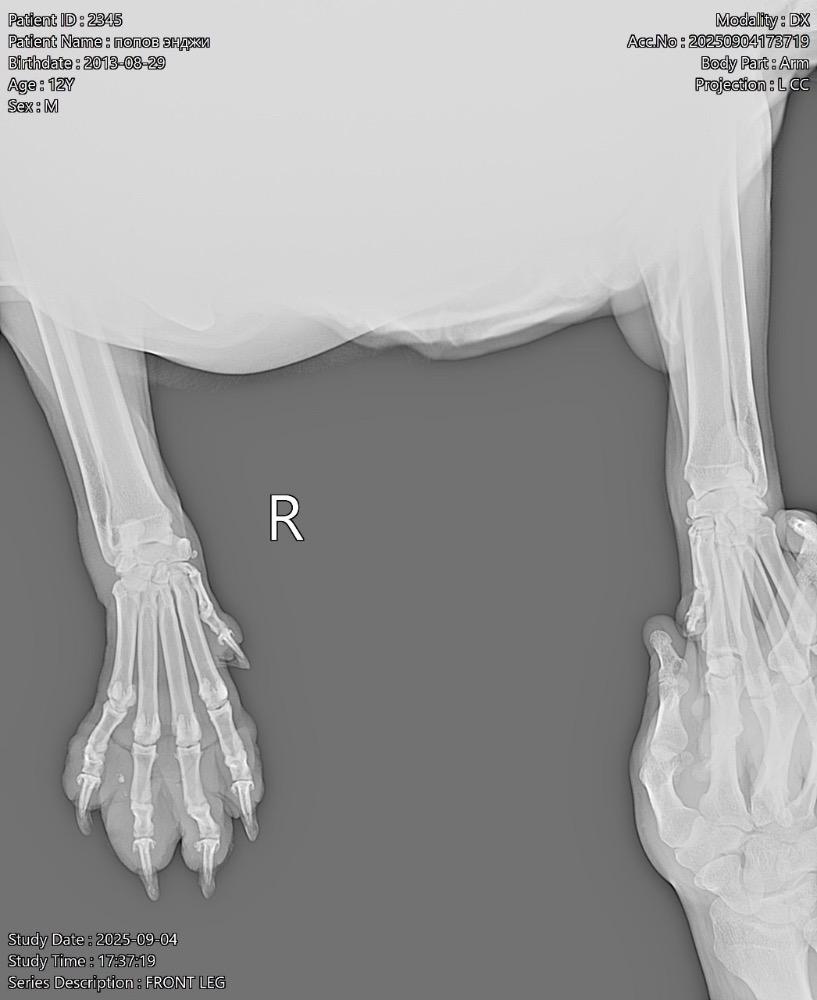

Татьяна13 Опубликовано 24 ноября, 2025 Опубликовано 24 ноября, 2025 (изменено) Всем здравствуйте! В июне началась проблема с лапами. Поставили диагноз-остеоартрит! Робексера+пк мерц прекрасно справлялись! На прошлой неделе собаке резко стало худо. Она начала часами без остановки дышать, иногда пристанывая. Было ясно, собаку что-то беспокоит…. В ветеринарке сдали анализ крови, сделали узи брюшной полости-ничего критичного… Врач решил, что Робексера уже не помогает, заменили на Фироко 227 мг + также оставили пк мерц. Добавили усросан, чтоб чуть полечить печень, так как небольшие отклонения есть… За 3 дня улучшений не вижу. Собака все также дышит без остановки часами, иногда пристанывая, второй день отказывается от корма (но вкусняшки ест), воду из миски пить отказывается (но пьет в ванной из душа и ест снег). Сегодня как будто начали отказывать задние лапы-она волочит ими. Вновь погнали в ветеринарку, они настаивают, что Фироко препарат хороший, сильнее его уже нет. Ждите! Чего ждать? Обезболивающее должно действовать же сразу…. Сказали, что тут скорее всего произошло защемление позвонка! Поэтому задние лапы не слушаются! И либо опять же ждите, либо делайте мрт, а потом операцию (собаке без пяти минут 12 лет, кстати!). Вдобавок выписали: Габапентин. В четверг хотят еще прокапать Хиовет. Сейчас, солнце мое спит, ходить не может. Когда просыпается, пытается встать и начинает дико плакать! И снова ложится! Люди, чем помочь собаке моей? Столько таблеток выписали… Как не навредить😭 У меня уже сердце болит… Изменено 24 ноября, 2025 пользователем Татьяна13 1